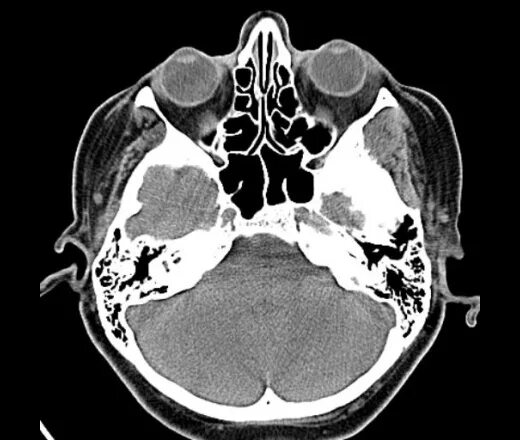

Череп на кт